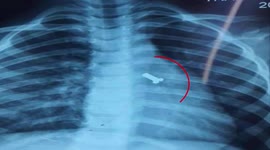

Vietnamese doctor removes pearl from 5-year-old boy's nose

A doctor removed a pearl from a 5-year-old boy's nose in Bac Giang in Vietnam.

The video, captured on October 13, shows Dr. Hoat using a tool to take a pearl out of a boy's nose.

According to the doctor, the boy's parents took the boy to his clinic as they said he inserted an object into his nose and the doctor discovered a round jewel in the boy's nose after a check-up.

Fortunately, the doctor removed the pearl from the boy's nose successfully and he was not hurt.